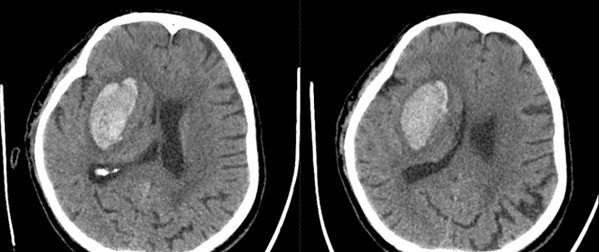

71歲的周先生突發(fā)左側肢體不能活動來醫(yī)院,頭部CT檢查發(fā)現(xiàn)腦出血,20多毫升的出血量不會危及生命,但左側肢體無法活動,考慮到促進肢體功能的恢復,進行了3D打印技術腦出血微創(chuàng)手術治療。

△可以看到出血量20余毫升,但腦室明顯受壓。

3D打印的導板可以精確直達血腫中心。